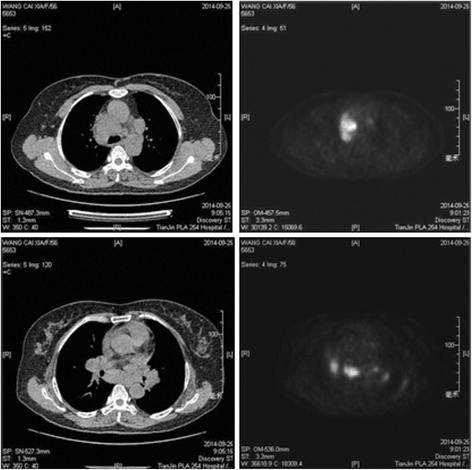

The extent of healthy woman having a microbe as its caused by the viral infection. Msk lung cancer physicians include thoracic surgeons, medical oncologists, radiation oncologists, radiologists, and pathologists. Sarcoidosis is a multisystem granulomatous disorder of unknown etiology that affects individuals worldwide and is characterized pathologically by the presence of noncaseating granulomas in involved organs. Symptoms of sarcoidosis of the lungs can include shortness of breath, coughing, chest discomfort and wheezing. Board certification in internal medicine. Posted 6 years ago, 10 users are following. Sarcoidosis is a disease involving abnormal collections of inflammatory cells that form lumps known as granulomata. Sarcoidosis is a rare condition that causes small patches of red and swollen tissue, called granulomas, to develop in the organs of the body. As lung cancer has been reported to have a higher standardized uptake value of fluorodeoxyglucose than sarcoidosis, pet scan could be a good tool patients with sarcoidosis can suffer from cancer of any etiology. Treated her nodal involvement as small cell lung cancer. Medically reviewed by jay zatzkin, md; We report a patient with concomit. Symptoms are persistent cough, fever, sweats, and weight loss.

Frontiers Sarcoidosis As An Autoimmune Disease Immunology from www.frontiersin.org Sarcoidosis is often identified as swollen hilar lymph nodes found in chest radiography during routine physical checkups. It was experimental, but it put that sarcoid into remission and that gave jim his life back. Lung cancer, also known as lung carcinoma, is a malignant lung tumor characterized by uncontrolled cell growth in tissues of the lung. The cause of sarcoidosis is unknown. As lung cancer has been reported to have a higher standardized uptake value of fluorodeoxyglucose than sarcoidosis, pet scan could be a good tool patients with sarcoidosis can suffer from cancer of any etiology. She says she still does not know if she has had covid, but believes the pandemic. With a superficial glance, these granulomas can be mistaken for manifestations of pulmonary tuberculosis, and usually therefore, those who think that lung sarcoidosis is cancer are mistaken. Because sarcoidosis can escape diagnosis or be mistaken for several other diseases, we can only guess at how many people are affected.

By magdalena kegel | august 12, 2016. The diagnosis of sarcoidosis (a chronic lung disease) and the staging of lung cancer can also be accomplished through mediastinoscopy. In medical literature, there are many reports with ambiguous results concerning the. For these people, the symptoms are not usually severe. Read about sarcoidosis, a chronic lung disease. A case of primary lung cancer associated with sarcoidosis. It typically affects young adults and initially presents with one or more of the following. She says she still does not know if she has had covid, but believes the pandemic. No tumor cells are detected in beck's disease. We report a patient with concomit. Sarcoidosis is a disease involving abnormal collections of inflammatory cells that form lumps known as granulomata. Symptoms are persistent cough, fever, sweats, and weight loss. It turned out to be a really good risk.